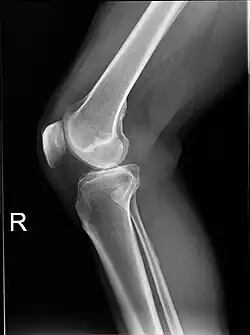

X-ray

-

Knee X-ray -

Knee X-ray (weight bearing) -

Knee X-ray (weight bearing, flexion)